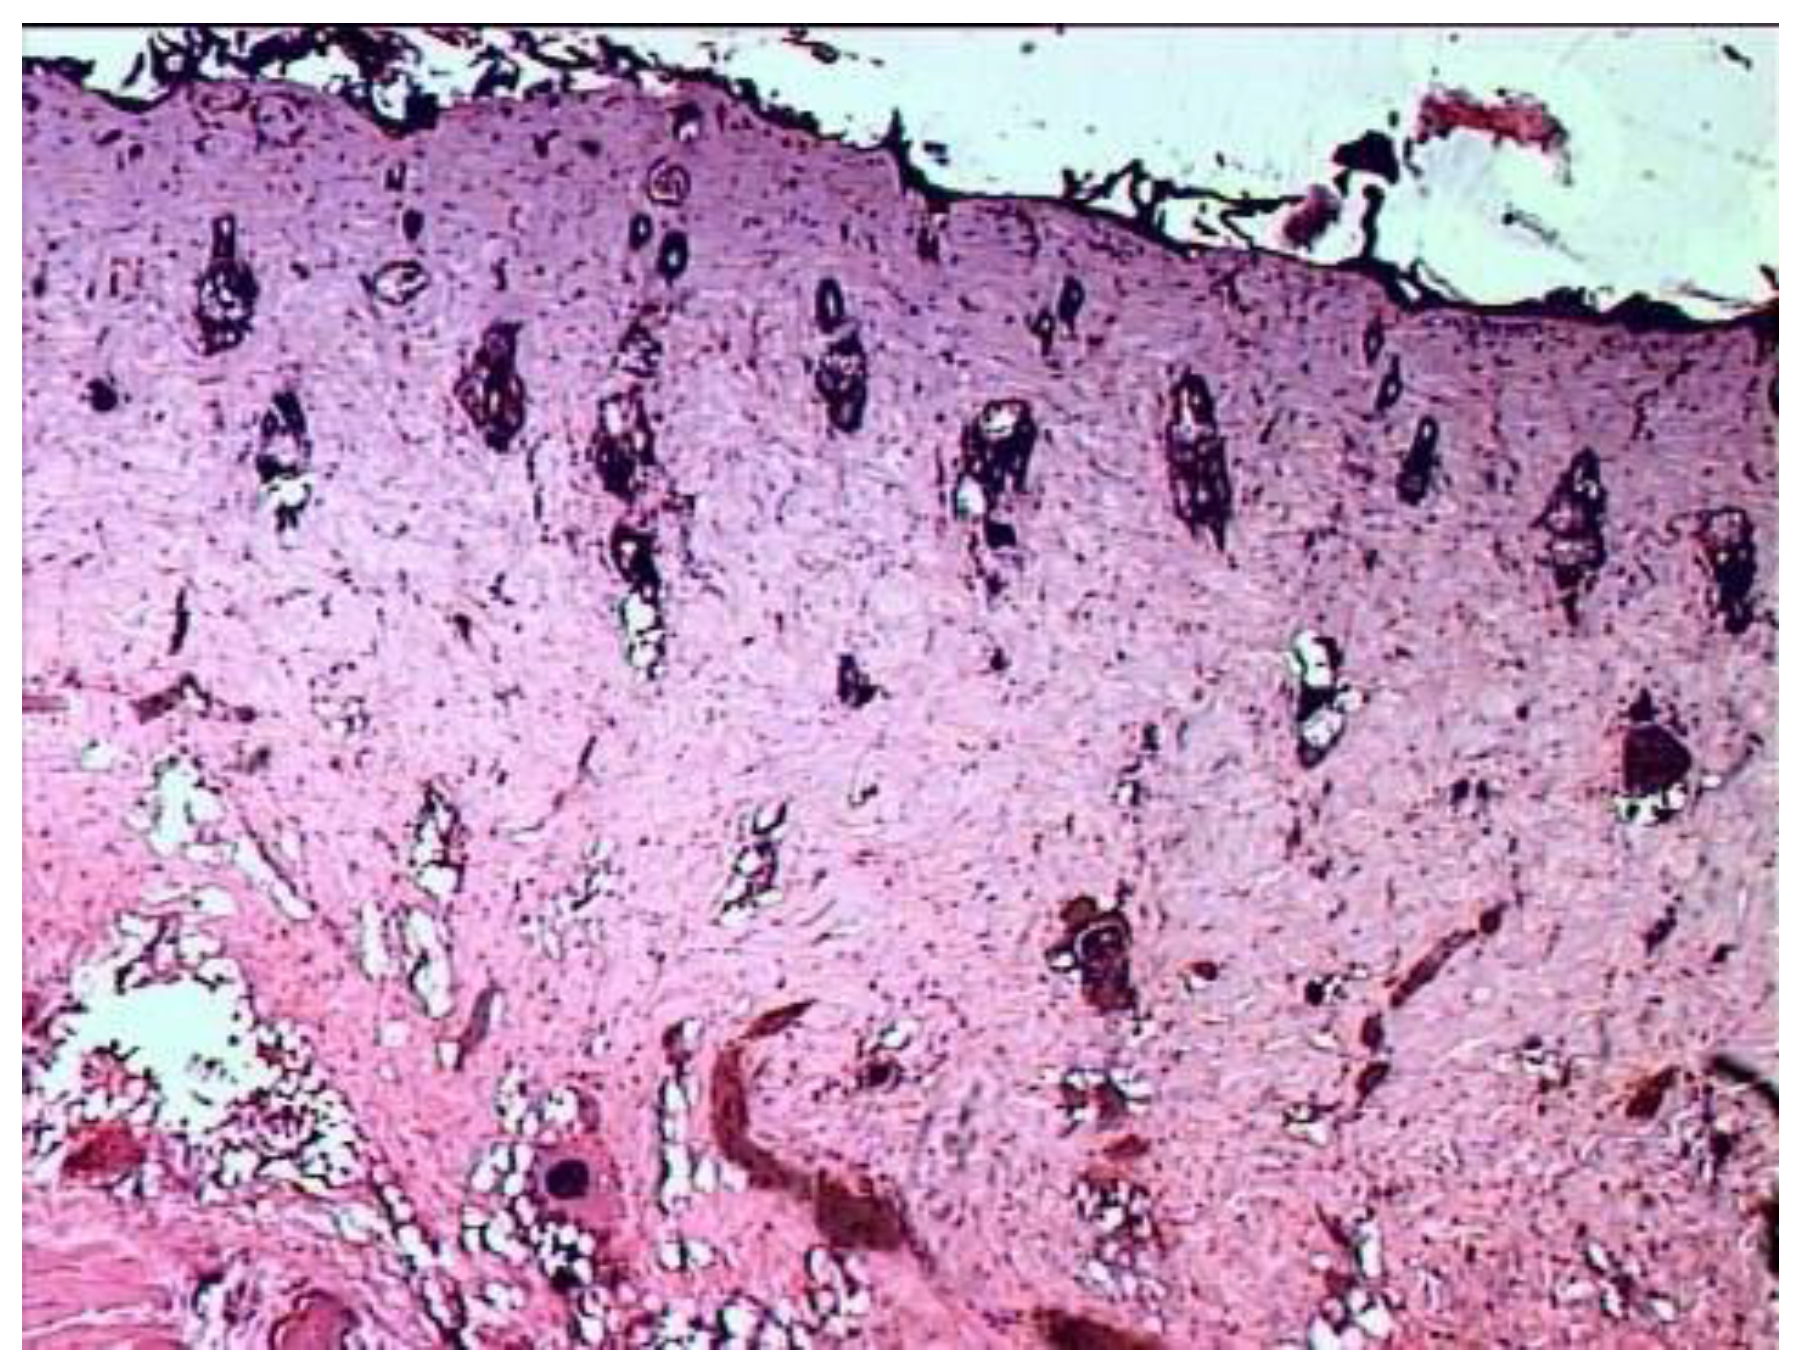

Fourteen days after the burn in the group of animals treated with ozonated oil, the scab on most of the wound surface is not separated from it (Figure 7). Purulent exudate is found under the scab. There is also a purulent discharge and fragments of necrotic tissues on the open (scab-free) surface of the wound.

The demarcation shaft in the part of the preparation (the center of the burn wound) passes directly over the layer of the skin’s own muscle, the muscle fibers of which are in a state of necrosis, necrobiosis or dystrophic changes. Part of the vessels passing over the muscle layer here is necrotic. Along the periphery of this zone, in the lower parts of the preserved dermis, in the layer of the skin’s own muscle and under it, there is a pronounced cellular reaction in the form of an accumulation of leukocytes (lymphocytes, neutrophils, eosinophils), macrophages, proliferating fibroblasts, which in some areas form young connective (granulation) tissue with single newly formed vessels. The muscle layer near the necrosis zone is in a state of rarefaction due to the death of muscle fibers and the proliferation of connective tissue cells and with the neoplasm of collagen fibers, but at the same time, muscle fibers with signs of regeneration (proliferation of nuclei, formation of muscle kidneys) are determined. Scarring of the wound is not pronounced; its epithelization is in its initial state. Thus, the use of ozonated oil for the treatment of a burn wound is accompanied by purulent inflammation, which is not limited to the formation of a demarcation leukocyte shaft, but also extends to the underlying tissues. The processes of scarring of the wound and its epithelization are weakened.

Figure 7. Morphological picture of burnt skin 14 days after the application of the burn when treating the wound with ozonated oil. Stained with hematoxylin and eosin. magn. ×50. (a) The scab is infiltrated by leukocytes and slightly separated from the wound surface. Purulent exudate accumulates under the scab (1—scab, infiltrated by leukocytes; 2—purulent exudate) (b) Weakly expressed marginal epithelization of the wound (1—scab with leukocyte infiltration; 2—purulent exudates; 3—creeping layer of regenerating epidermis; marginal epithelization; 4—edematous underlying tissue).